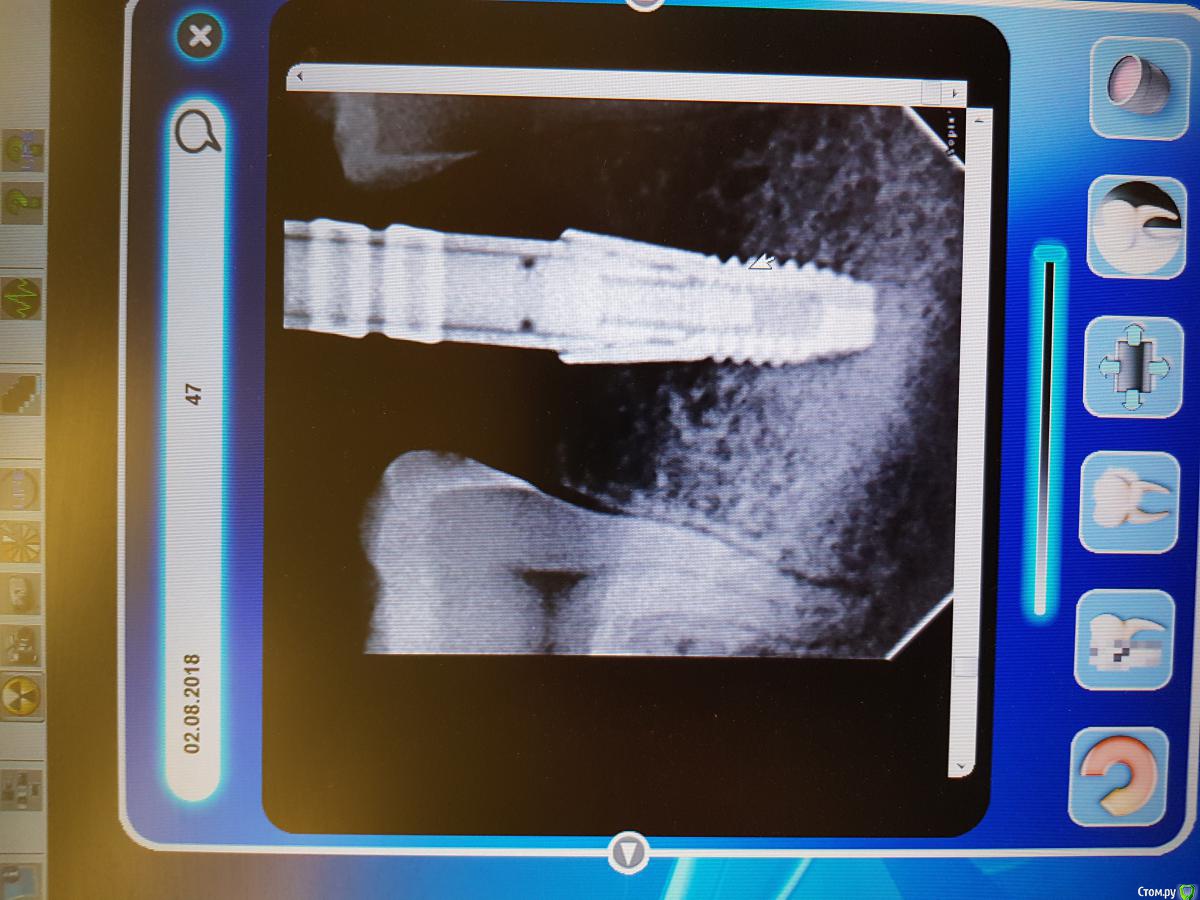

Kazankov.Egor Опубликовано 5 августа, 2018 Поделиться Опубликовано 5 августа, 2018 (изменено) Сабж, вотс имплант не определил. Загрузчик развернул фото, поправить не получается. Изменено 5 августа, 2018 пользователем Kazankov.Egor Ссылка на комментарий

red_butler Опубликовано 5 августа, 2018 Поделиться Опубликовано 5 августа, 2018 астра TX широкая платформа 2 Ссылка на комментарий

Bier Опубликовано 7 августа, 2018 Поделиться Опубликовано 7 августа, 2018 согласен, Астра широкая. Ссылка на комментарий